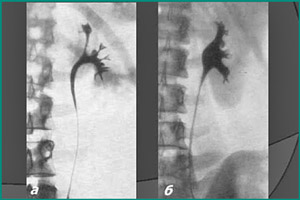

Ретроградная или восходящая урография – это процедура рентгеновского исследования верхних мочевыводящих путей, при которой вводится водорастворимое контрастное вещество через катетер, вставленный в уретру. Во время этой процедуры выполняется серия рентгеновских снимков, называемая урограммой, чтобы визуализировать органы и выявить наличие конкрементов, кистозных и опухолевидных образований. Кроме этого, иногда выполняется антеградная или нисходящая урография, при которой контрастное вещество вводится в лоханку через прокол, если невозможно ввести непроницаемый раствор через уретру.

Снимки делаются в положении лежа и стоя в прямой, а при необходимости – в косой и боковой проекциях. Это позволяет максимально заполнить полость лоханки контрастным раствором и провести качественное исследование. Повторные снимки делаются через час после введения контраста для оценки выделительной функции мочевыводящей системы.